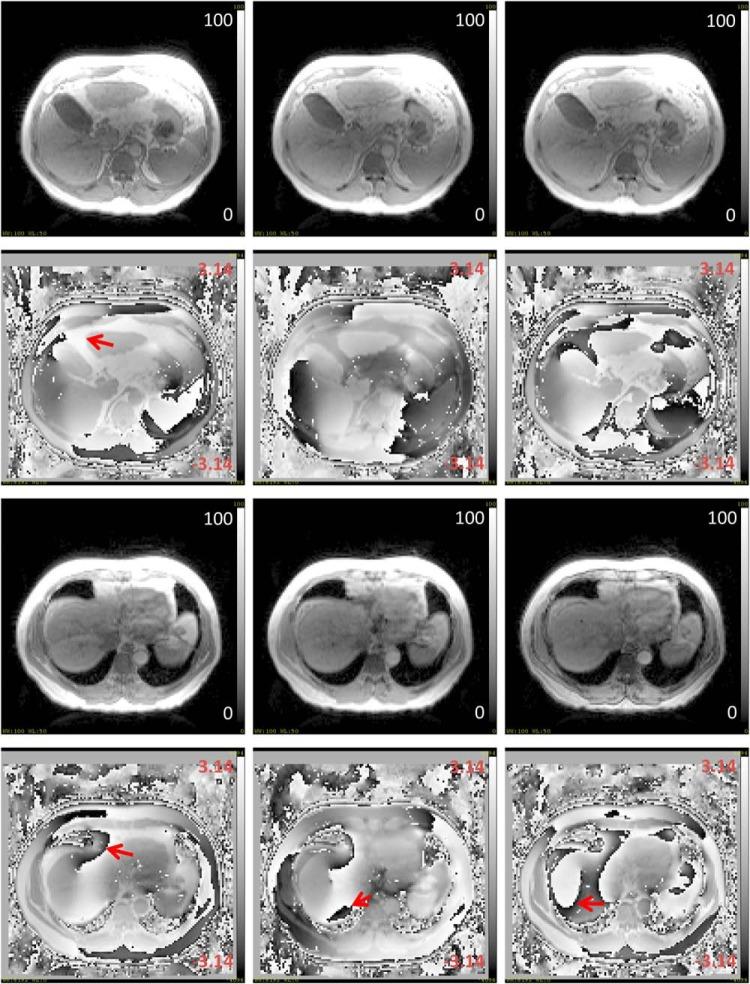

We developed an optimized and robust method to estimate liver B0 field inhomogeneity for monitoring and correcting susceptibility-induced geometric distortion in magnetic resonance images for precision therapy. A triple-gradient-echo acquisition was optimized for the whole liver B0 field estimation within a single-exhale breath-hold scan on a 3 T scanner. To eliminate chemical-shift artifacts, fat signals were chosen in-phase between 2 echoes with an echo time difference (ΔTE) of 2.3 milliseconds. To avoid phase-wrapping, other 2 echoes provided a large field dynamic range (1/ΔTE) to cover the B0 field inhomogeneity. In addition, using high parallel imaging factor of 4 and a readout-bandwidth of 1955 Hz/pixel, an ~18-second acquisition time for breath-held scans was achieved. A 2-step, 1-dimensional regularized method for the ΔB0 field map estimation was developed, tested and validated in phantom and patient studies. Our method was validated on a water phantom with fat components and air pockets; it yielded ΔB0-field maps that had no chemical-shift and phase-wrapping artifacts, and it had a <0.5 mm of geometric distortion near the air pockets. The ΔB0-field maps of the patients' abdominal regions were also free from phase-wrapping and chemical-shift artifacts. The maximum field inhomogeneity was found near the lung-liver interface, up to ~300 Hz, resulting in ~2 mm of distortions in anatomical images with a readout-bandwidth of 440 Hz/pixel. The field mapping method in the abdominal region is robust; it can be easily integrated in clinical workflow for patient-based quality control of magnetic resonance imaging geometric integrity.

我们开发了一种优化且稳健的方法,用于估计肝脏B0场不均匀性,以监测和校正磁共振图像中由磁化率引起的几何畸变,从而实现精准治疗。在3T扫描仪上进行单次屏气扫描时,对三重梯度回波采集进行了优化,以用于全肝脏B0场估计。为消除化学位移伪影,在两个回波之间选择脂肪信号处于同相状态,回波时间差(ΔTE)为2.3毫秒。为避免相位缠绕,另外两个回波提供了较大的场动态范围(1/ΔTE)以覆盖B0场不均匀性。此外,使用4的高并行成像因子和1955Hz/像素的读出带宽,屏气扫描的采集时间约为18秒。开发了一种用于ΔB0场图估计的两步一维正则化方法,并在体模和患者研究中进行了测试和验证。我们的方法在含有脂肪成分和气腔的水模上得到了验证;生成的ΔB0场图没有化学位移和相位缠绕伪影,并且在气腔附近的几何畸变小于0.5毫米。患者腹部区域的ΔB0场图也没有相位缠绕和化学位移伪影。在肺-肝界面附近发现最大场不均匀性高达约300Hz,在读出带宽为440Hz/像素的解剖图像中导致约2毫米的畸变。腹部区域的场映射方法很稳健;它可以很容易地集成到临床工作流程中,用于基于患者的磁共振成像几何完整性质量控制。